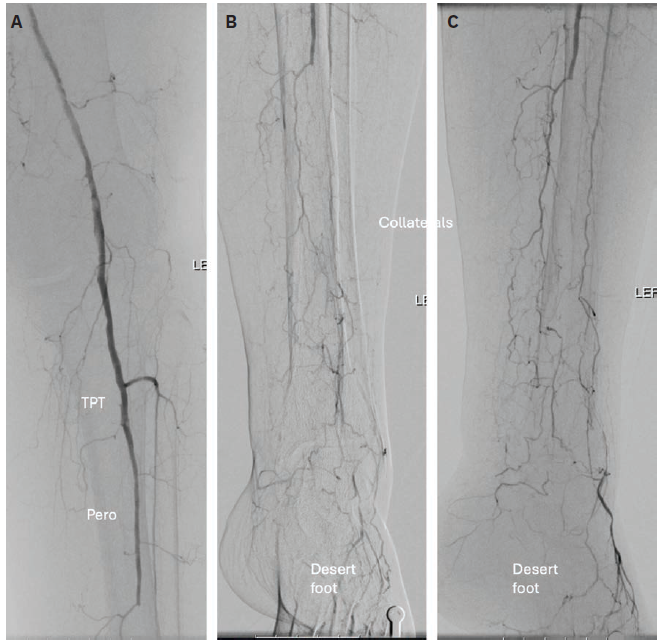

Plantar venography confirmed a complete plantar venous arch (Figure 3A). Angiography showed an ostial occlusion in the left posterior tibial artery. The ostial posterior tibial artery lesion was crossed with a Command 14 wire and CXI microcatheter (Cook Medical), and then dilated with a 3.0 mm x 120 mm

peripheral balloon (Figure 3B). Repeat angiography indicated a potential crossover segment at the proximal posterior tibial artery. A 5 mm x 100 mm peripheral balloon was advanced from the left lateral plantar vein to the left cranial posterior tibial vein to cross over the segment, and was dilated to mark the posterior tibial vein. Using the ARC device (LimFlow), the Nitrex wire (Medtronic) was crossed from the posterior tibial artery to the posterior tibial vein under fluoroscopy guidance (Figure 3C). The posterior tibial artery-posterior tibial vein crossover site was dilated with a 3.5 mm x 120 mm balloon (Figure 3D). Vector valvulotome (forward-cutting) (LimFlow) was used to destroy the valves of the posterior tibial vein. The posterior tibial vein-lateral plantar vein was stented with 5.5 mm x 150 mm (LimFlow) covered stents (two stents were placed) (Figure 4A). The posterior tibial artery-posterior tibial vein crossover site was stented with a 3.5 mm x 60 mm tapered covered stent (LimFlow) (Figure 4A). The stents were dilated with a 5.0 mm x 150 mm peripheral balloon in the venous segment and a 3.5 mm x 120 mm peripheral balloon in the arterial segment (Figures 4B-C).